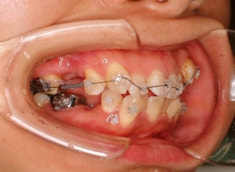

治療開始時